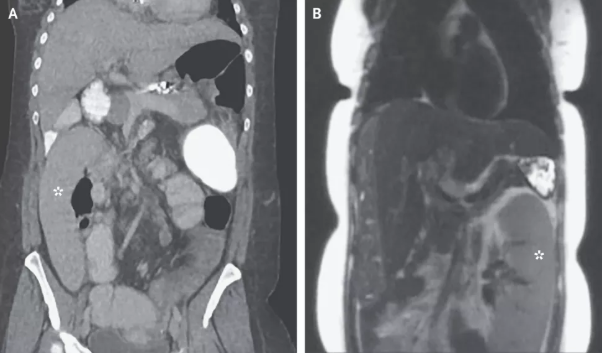

密歇根醫(yī)學(xué)院內(nèi)科醫(yī)生Alexander Wester博士介紹,脾臟是人體內(nèi)負(fù)責(zé)過濾血液并提供免疫力的器官,通常位于腹部左上位置,胃部上方。但是,這名36歲婦女的影像學(xué)結(jié)果顯示,她的脾臟出現(xiàn)在了腹部右下位置。

巧合的是,這名婦女剛剛做了肝癌篩查,影像學(xué)報(bào)告中的脾臟還是正常的,位于身體左側(cè)(圖B)。她檢查之后的第一天出現(xiàn)了腹痛和嘔吐,第二天再做一次檢查,脾臟向右跑了0.3米(圖A)。

Wester解釋,這是一種罕見的疾病,稱為“脾臟漂移”。這名婦女患有一種叫做“原發(fā)性硬化性膽管炎” 的肝臟疾病,由于膽管發(fā)炎可造成嚴(yán)重的肝臟疤痕,導(dǎo)致肝硬化,使血液流動(dòng)能力受阻。血管堵塞導(dǎo)致血液回流,受影響最嚴(yán)重的部位就是脾臟。隨著時(shí)間推移,脾臟容納血液增多,變得越來越大,周圍的韌帶被拉伸松弛,使脾臟脫離上腹部的位置,跑到別處去了。